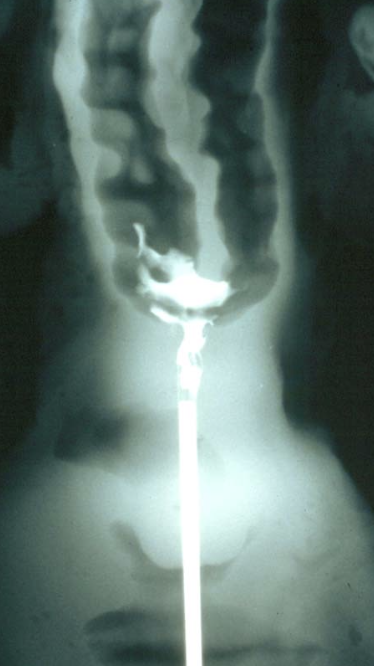

where is the correct placement of semen in the bovine female reproductive tract?

body of the uterus (between the internal os of the cervix and the bifurcation)